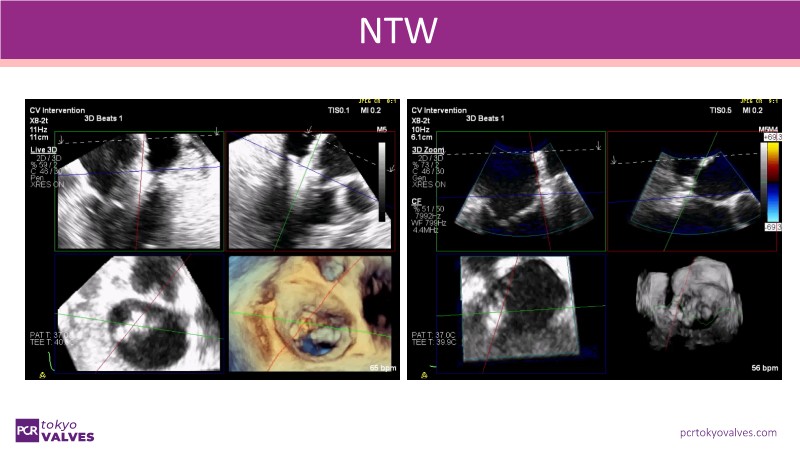

Explore the latest advancements in TEER therapy with this PCR Tokyo Valves 2025 session dedicated to MitraClip. Through expert-led case discussions, gain a deeper understanding of complex scenarios, including restricted posterior leaflet in functional mitral regurgitation, commissure lesion (A3P3), and MitraClip combined with Amulet.

This session also highlights key findings from the OCEAN study, shedding light on 1-year heart failure rehospitalisation outcomes with MitraClip. Additionally, discover how atrioventricular valve morphology impacts treatment strategies and how the four available clip sizes can be used to personalise and optimise TEER outcomes.